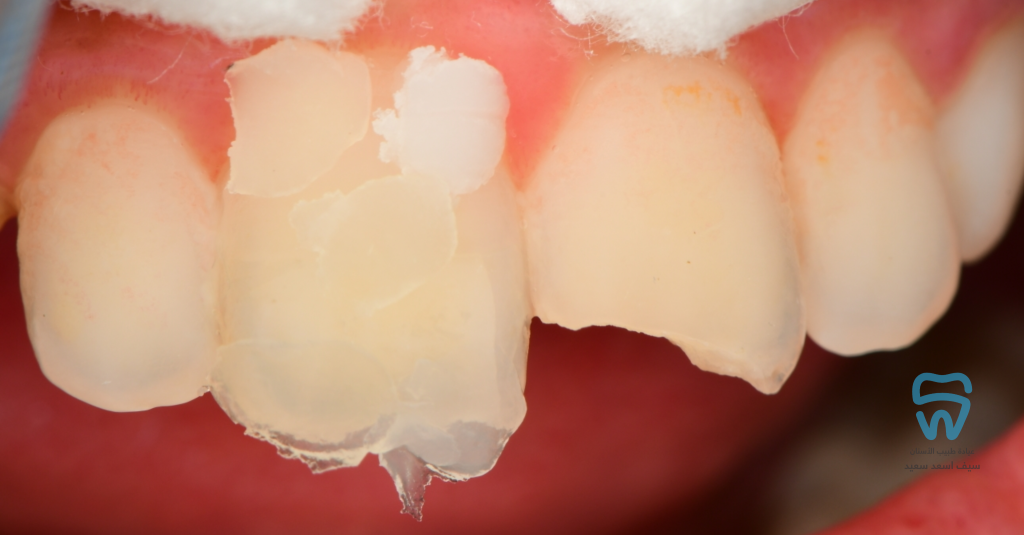

patient came with 2 fractured upper centrals

closer look at the condition

The fractured segment of the right central